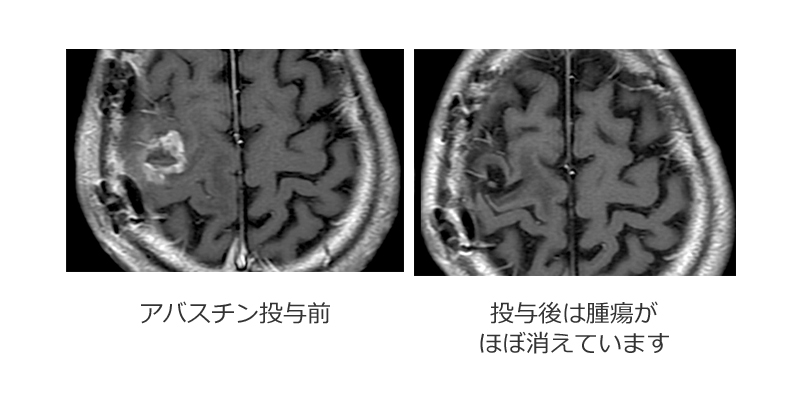

神経膠腫にも多くの種類がありますが、その中から最も悪性度の高いgrade4の膠芽腫を紹介します。この腫瘍は周囲の正常脳に入り込む性質(浸潤性)があるため、手術で完全に取り切ることが難しく、腫瘍細胞がまわりの脳に残ってしまいます。従って術後に放射線治療や化学療法が必要になります。このように治療困難な腫瘍に対しても、当科では効果の高い新しい薬(分子標的薬;アバスチン)などを用いて積極的に治療に取り組んでいます。そして非常に良い結果を出しています。